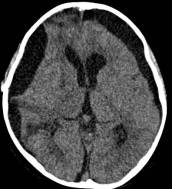

病例二:患儿女性,7岁,主因头痛2年,精神差1个月收入院。入院时头CT见典型的“超大型”颅咽管瘤,直径约9厘米,见图6。

图6.CT显示囊性颅咽管瘤

白色三角显示肿瘤边界